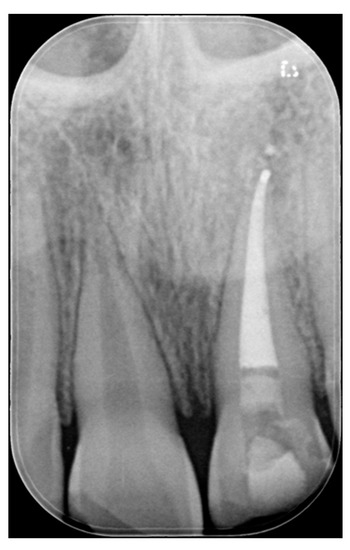

Figure 2.

Initial x-ray. Reprinted from Restauri diretti nei settori anteriori, G. Paolone, S. Scolavino, © 2021, with permission from Quintessence Publishing Italy.